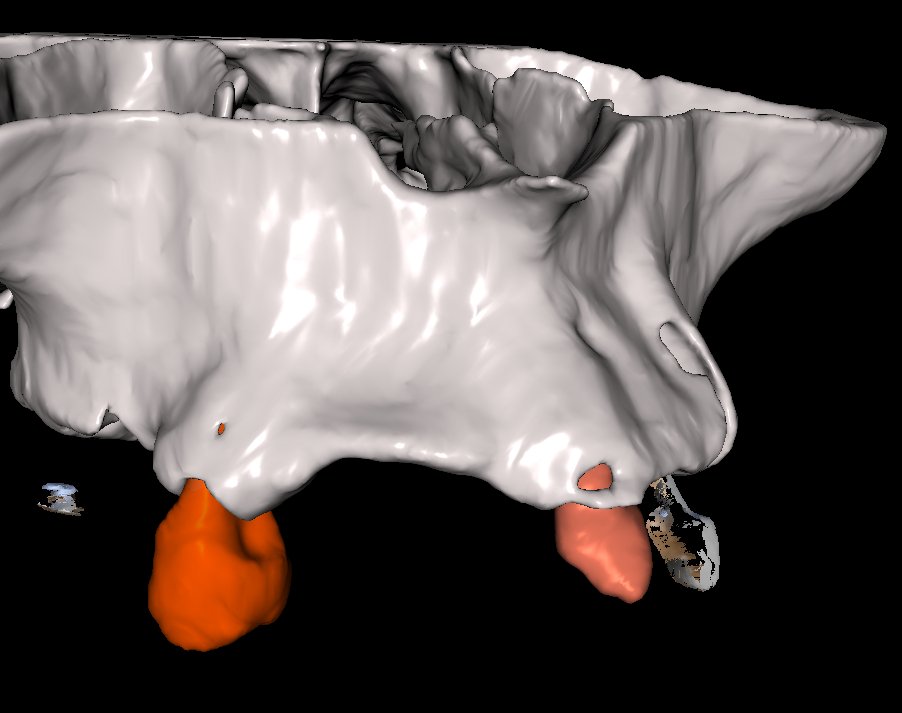

• Diagnóstico tomográfico (CBCT): lectura enfocada en regeneración ósea.

• Análisis del defecto óseo: tipo, morfología y severidad.

• BlueSkyPlan: diagnóstico, segmentación y análisis del defecto.

• Segmentación ósea y dental.

• Generación del defecto virtual.

• Control tridimensional del volumen a regenerar.